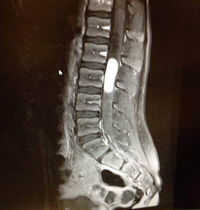

Morissa was sleeping when the nurse told me this information. My head was spinning. A tumor? She did use the words “mass” and “tumor”! I broke down. I called my family for support and my mom was there in less than five minutes. The ambulance transported us to a children’s hospital and the ride was bumpy and painful for my little girl who had a mass in her spinal canal! Getting to the next hospital was just the beginning of our journey. Knowing that we had one of the top pediatric neurosurgeon’s in the U.S. operating on my daughter was of great comfort. He was very nice and explained things in a way that Morissa and I could understand. She was glad to hear the pain would be gone! He thought the tumor was a myxopapillary ependymoma (which was later confirmed) and there was little information available for this rare tumor. The night before her surgery was scheduled, she lost control of everything from the waist down. That was a scary moment for her… and for us! I had to be the calm mommy. The tumor she had was very large according to the doctor, pressing on all the nerves in the lumbar region. The possible risks of surgery were scary – it was a minute-to-minute and day-to-day process. She had a gross total resection and her follow-up MRI’s were clear.

In August 2014, the neurosurgeon saw a spot of concern. We didn’t know, and no one told us, until May 4, 2015 that it had grown! They had only been doing lumbar MRI’s and finally decided to get a full spine and brain MRI. The tumor in the lumbar showed growth, and they also found more tumors in thoracic spine. So they immediately made plans for treatment of those, at MD Anderson Cancer Center Children’s Hospital. We met with her neuro-oncologist, Dr. Khatua and started proton beam radiation.